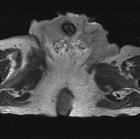

An

extraordinary case of Buschke–Lowenstein tumor: multiple localization, malignant transformation, and clinical insights—a case presentation and literature review. MRI image of the perineal and inguinal lesions

An

extraordinary case of Buschke–Lowenstein tumor: multiple localization, malignant transformation, and clinical insights—a case presentation and literature review. MRI image of the perineal lesion